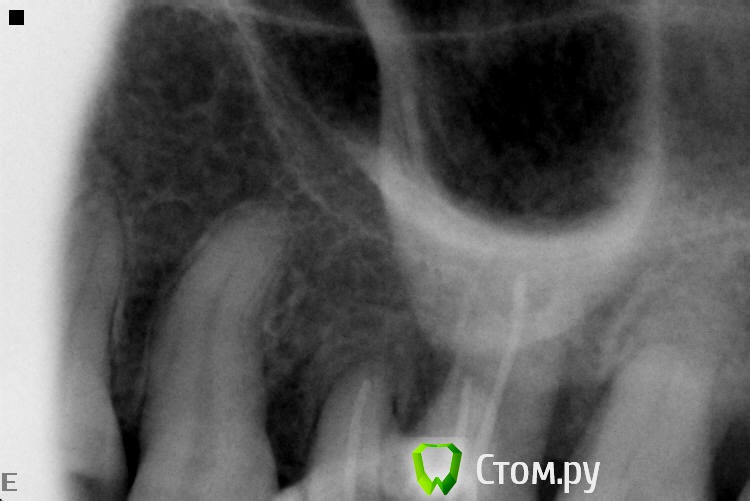

SDC Опубликовано 2 октября, 2014 Поделиться Опубликовано 2 октября, 2014 (изменено) Ой, колонет он его. Фиссуры, знатно нарезанные по проксимальной оси, активно способствуют этому. Присоединяюсь к Маэстро (можно русскими буквами?) по кофферу и добавлю про зубной камень. Сначала проф. г. Изменено 2 октября, 2014 пользователем SDC Ссылка на комментарий

M@estro Опубликовано 2 октября, 2014 Поделиться Опубликовано 2 октября, 2014 Ой, колонет он его. Фиссуры, знатно нарезанные по проксимальной оси, активно способствуют этому. Присоединяюсь к Маэстро (можно русскими буквами?) по кофферу и добавлю про зубной камень. Сначала проф. г. Можно, не забивайте голову. Я уж про мелочи типа "накладки" не стал писать , основное бы выяснить Дистальная сохранена,не так быстро кольнёт,но вероятность велика,да и медиальный перерасширен. Ссылка на комментарий

Slaggy Опубликовано 2 октября, 2014 Автор Поделиться Опубликовано 2 октября, 2014 (изменено) Ой, колонет он его. Фиссуры, знатно нарезанные по проксимальной оси, активно способствуют этому. Присоединяюсь к Маэстро (можно русскими буквами?) по кофферу и добавлю про зубной камень. Сначала проф. г. В клинике кофферы что есть - личные. Сегодня в начале дня доел последний, а пациент вечером был. ((( Верхняя челюсть - пылесос и валики. Снимки утромбовав тефлоном или гутта и временная пломба. Все почти по феншую. ПОЧТИ )) Ultimate, толсто сделал эмаль. Не расколет. Стенки сохранены все.Про вкладки и накладки - в наших лесах это редкость. Вся клиника собирается посмотреть, когда безметалл ставлю. Туго тут. ))) Пациент пришел с болями после удаления. Не до гигиены было. Сразу в бой. Теперь разговоры об имплантах, санации и гигиене. Изменено 2 октября, 2014 пользователем Slaggy 1 Ссылка на комментарий

Slaggy Опубликовано 2 октября, 2014 Автор Поделиться Опубликовано 2 октября, 2014 (изменено) Ну почётно,что тут скажешь. Вы сами знаете, что подтянуть. Но зуб я всё -таки покрыл бы в итоге,когда дойдёт до протезирования. Да все тянуть надо, при этом 10-12 пациентов в день.Сегодня 3 эндотрупа моляров работаны, Один свежий пульпит , 3 сдачи/фиксации, 1 съемник и 1 профгигиена. Про эндотрупы: ушел под кальцийКстати, это еще приличные снимки. обычно любуюсь апикальной третью корней ))))Тут в резорцинке косяк произошел. Видимо при конденсации проскочила гутта ((( расстроился.Но её хирург протежировал, Поговорю с ним, если апико сделает, то я не полезу. Изменено 2 октября, 2014 пользователем Slaggy 1 Ссылка на комментарий